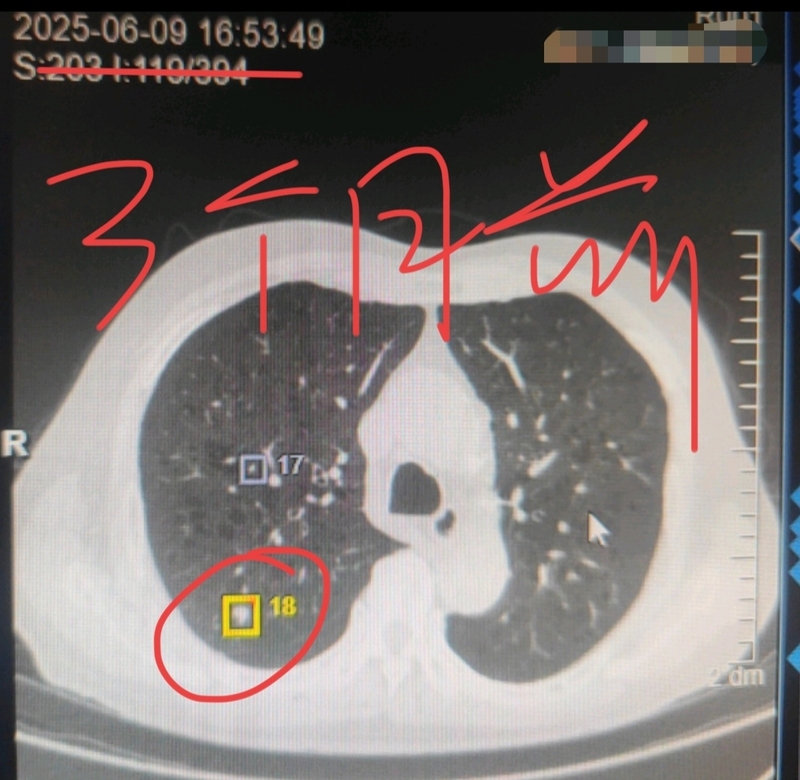

劉懿博士說肺癌(一〇一六一)實性肺結節(jié)吃幾十元藥三個月后變小

三個月前,有一位來自東北的男士在家人陪伴下過來找我看病。他因為咳嗽拍片子,發(fā)現(xiàn)了雙肺都有結節(jié)。最大的結節(jié)在右肺上葉,直徑8mm,是一個實性的,其他的結節(jié)也都是實性的居多。我看到他的片子,肺質量不好,問他是不是抽煙?他說自己抽煙時間很長,量也不少,我告訴他今后一定要戒煙。同時根據他的肺結節(jié)情況,給他安排抗炎治療,也就幾十塊錢的事。告訴他吃完藥之后,按照我說的時間來醫(yī)院復查。一晃三個月就過去,他按照計劃又復查了一下,發(fā)現(xiàn)之前的肺結節(jié)都減小了,有些還消散了。最大的那個八毫米肺結節(jié)現(xiàn)在變成了五毫米,別看從數(shù)值上看才小了三毫米,但是體積縮小了好幾倍,大家從CT片子上也可以看出來,這個肺結節(jié)顯著變小。這樣的變化說明他的肺結節(jié)炎癥性的可能性最大,我建議他半年后再復查。大家發(fā)現(xiàn)肺里有結節(jié),一定要先找正規(guī)醫(yī)院的醫(yī)生看一看,即使安排抗炎治療的話,也就幾十塊錢的事,根本就不需要每個月花好幾千甚至上萬元錢去熬藥喝散結,那么多錢能辦到的事,幾十塊錢的消炎藥也能辦到。大家不要為自己的認知交不必要的智商稅。